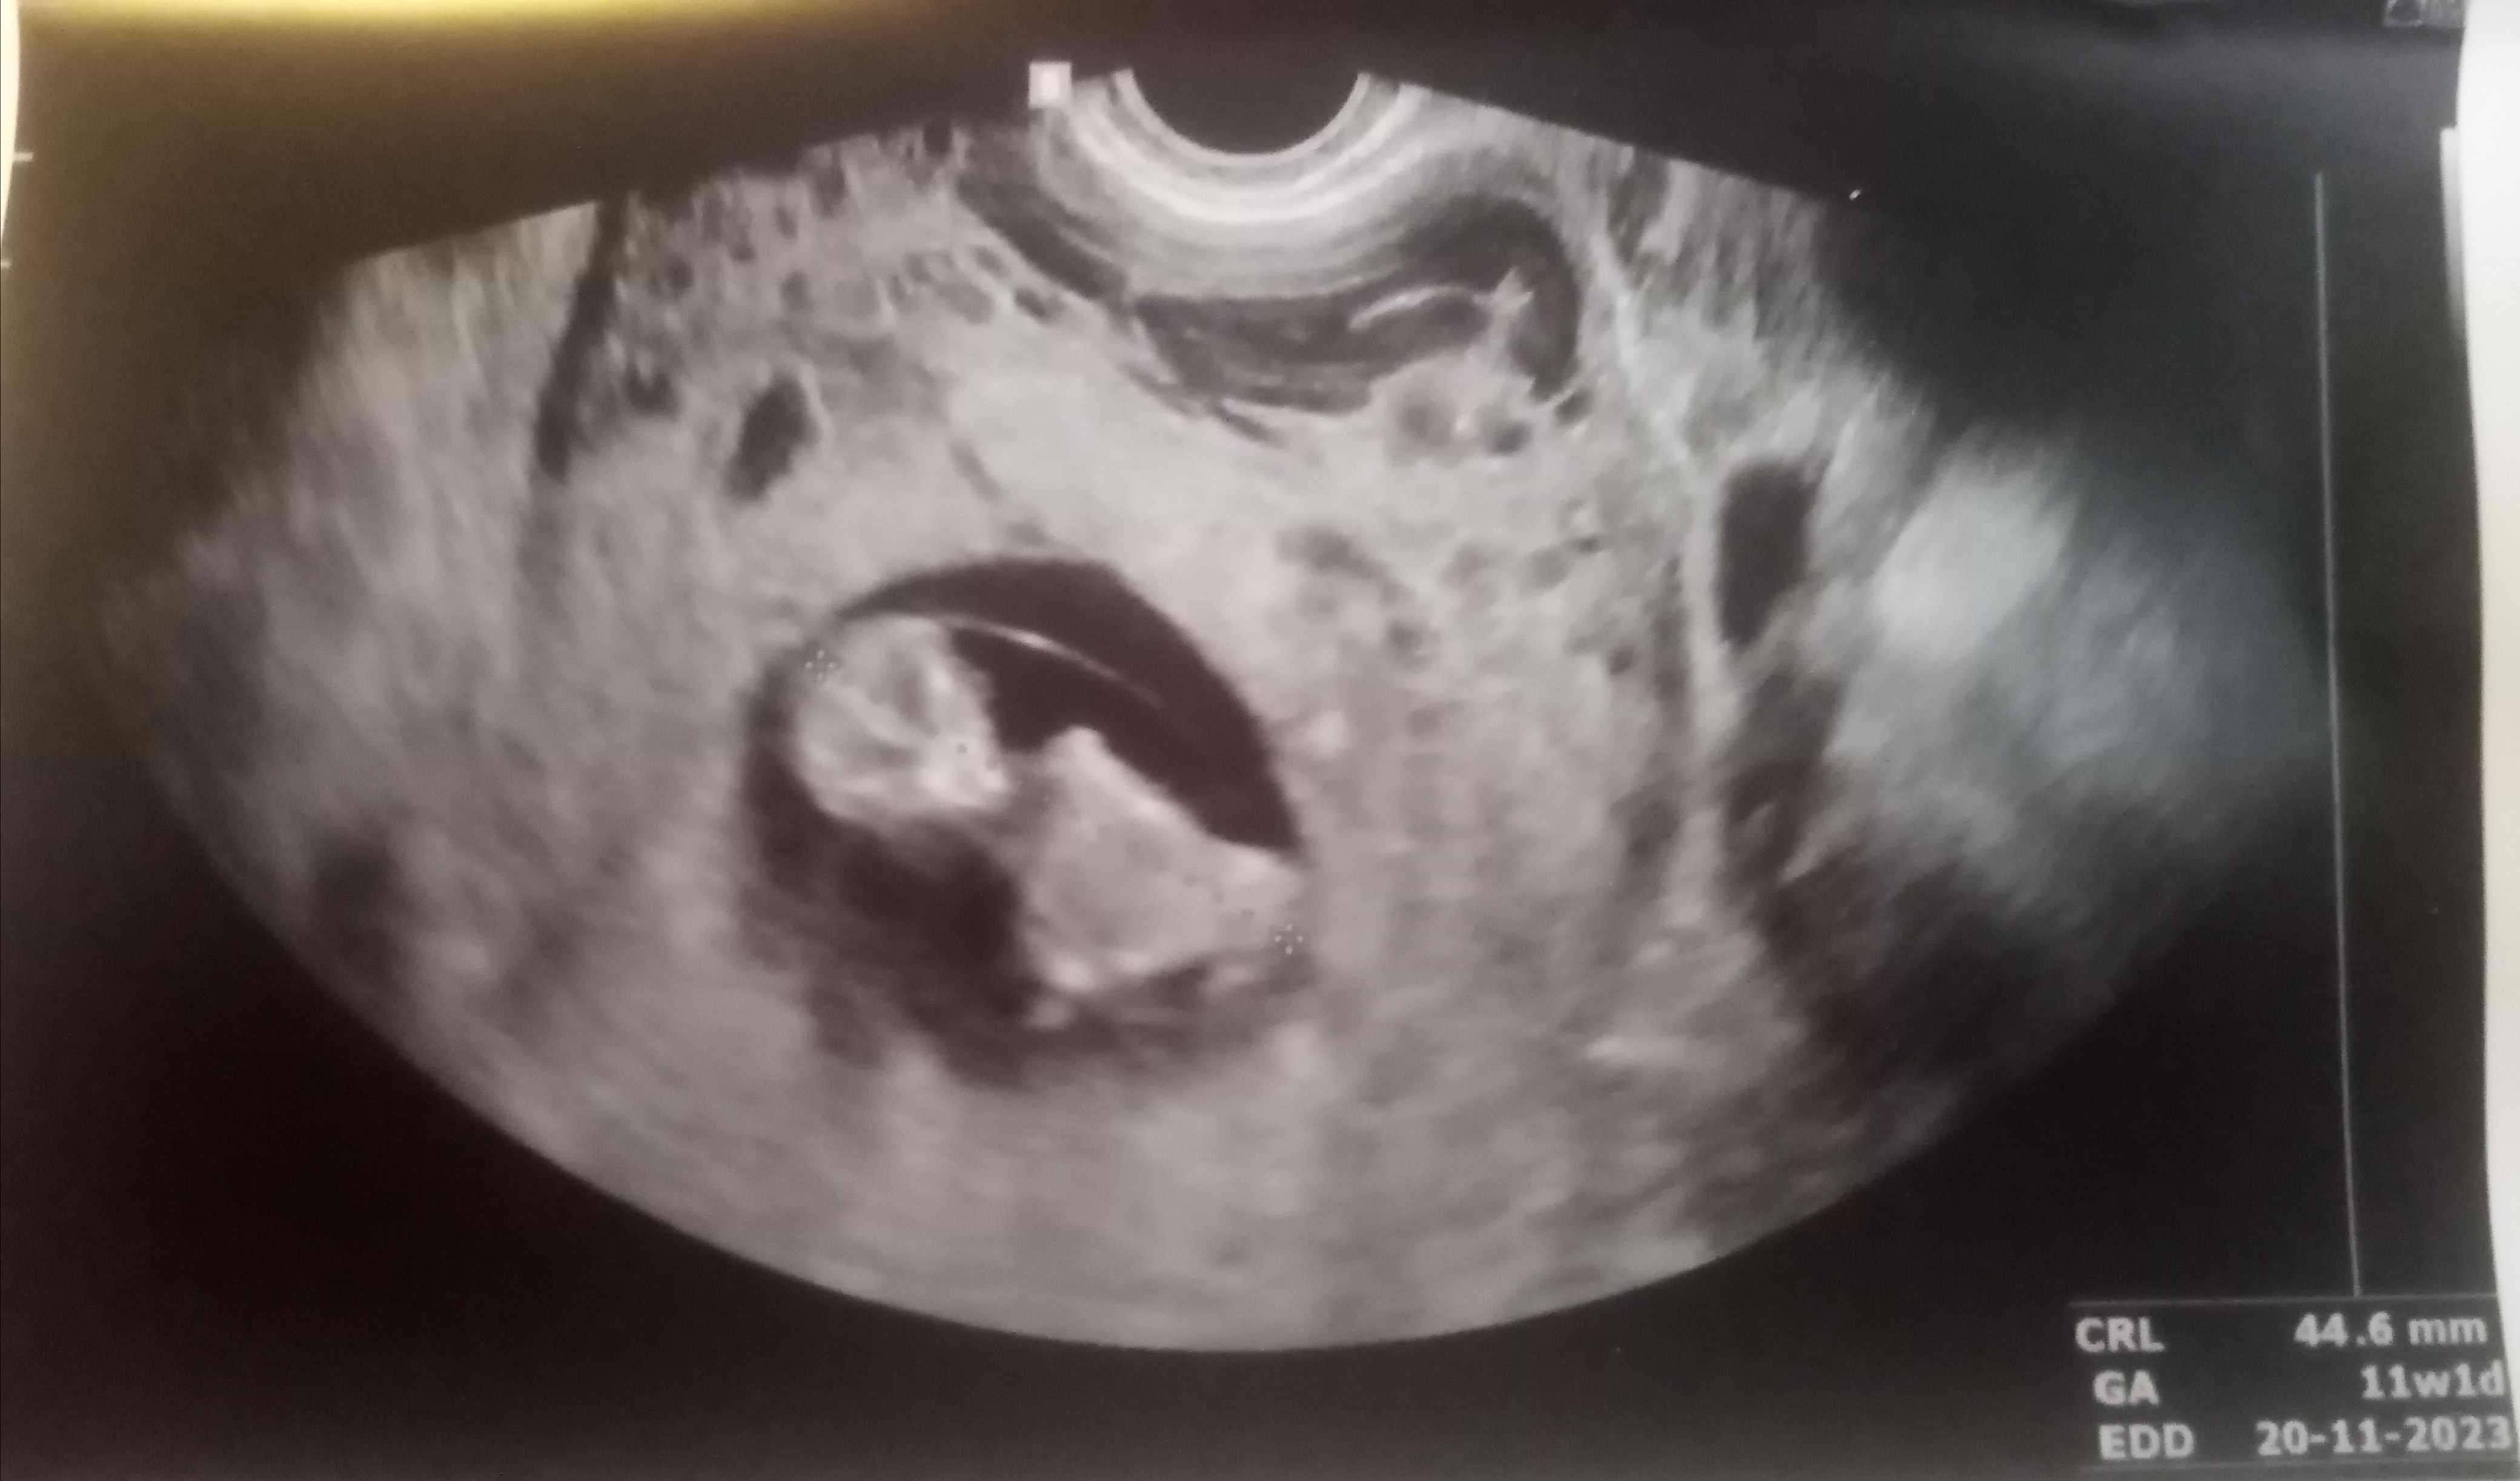

@lepus timidus Mikä ihana viipottaja siellä näkyykään

Varmaan pikku pääkallokaveri jo säästeli äidin hermoja kun ei antanut tarkkoja mittoja. Ajatteli varmaan että kuitenkin äiti taas menee sinne BBT-palstalle huolesta soikeena ylianalysoimaan mun mittoja niin parempi että viuhdon menemään niin että kätilö ei pysy viivottimen kanssa perässä

Hienoa että kaikki siellä hyvin